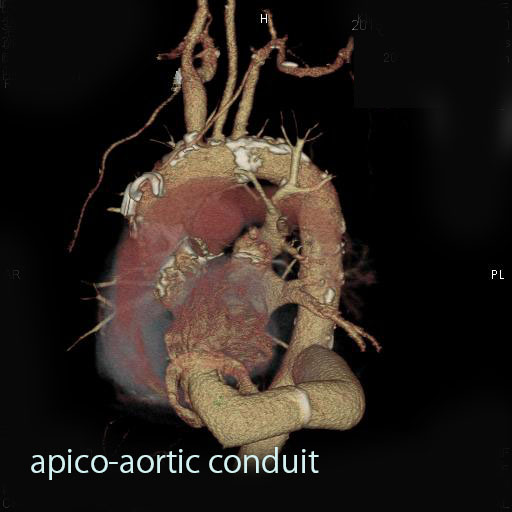

| 胸部大動脈手術 | 18 | 20 | 19 | 22 | 29 | |

| ステントグラフト | 0 | 1 | 1 | 7 | 9 | |